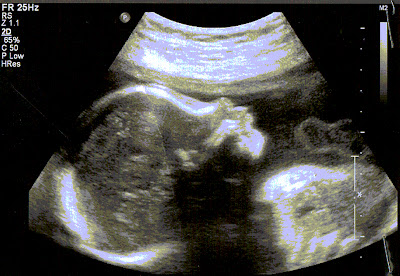

| 27 wks |